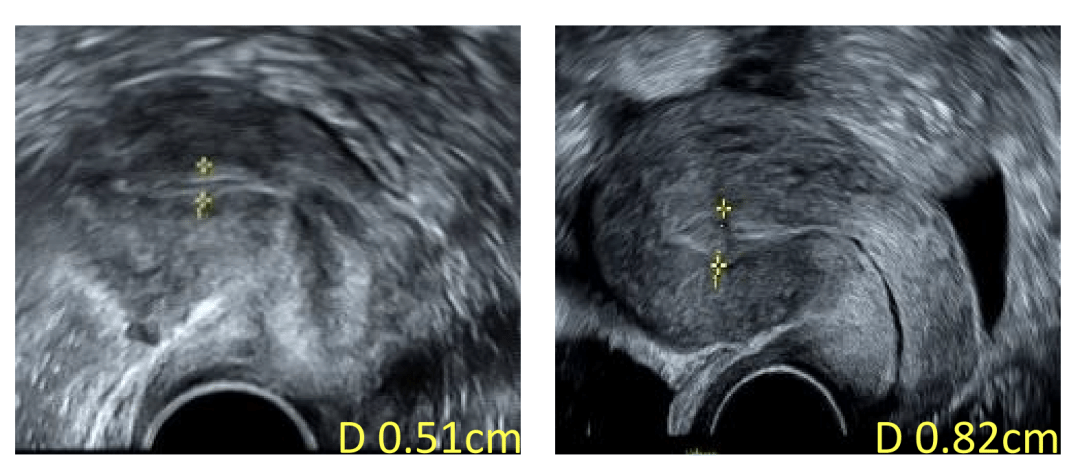

治疗后,子宫内膜厚度(右)较治疗前(左)明显改善

治疗后,王女士子宫内膜厚度得到明显改善,术后第二个月内膜厚度即超过8毫米。